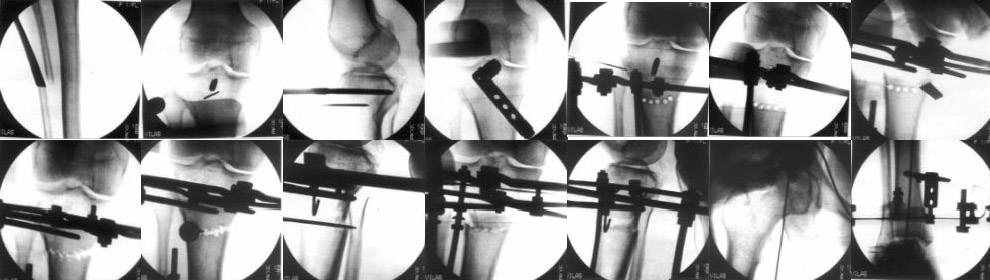

Sending you pics of the steps of the osteotomy and the frame.

You can do the osteotomy in a "focal dome" or in a transverse fashion. The dome has the advantage of having a good contact, allowing weight bearing as tolerated early on.

The level is below the tibial tuberosity.

The frame I use is pretty simple, with one wire each in the proximal and distal ring, two schanz pins in the proximal ring, and one each in the middle and distal ring.

I preconstruct a frame with the proximal ring in varus by the use of coupled washers in the threaded rods in the front and back. These are used as hinges, and after the correction, a medial and lateral threaded rod is also added.

Since the center of rotation of these deformities is usually near the knee joint line, lateral translation of the distal fragment is necessary to normalise all the axes.

You can also do the osteotomy in a transverse fashion.

When I use an orthofix fixator, the osteotomy is oblique, starting below the tuberosity and ending 1 cm away from the lateral cortex at the level of the head of the fibula. No fibular osteotomy is needed there. The deformity is gradually corrected over 2 or three weeks.